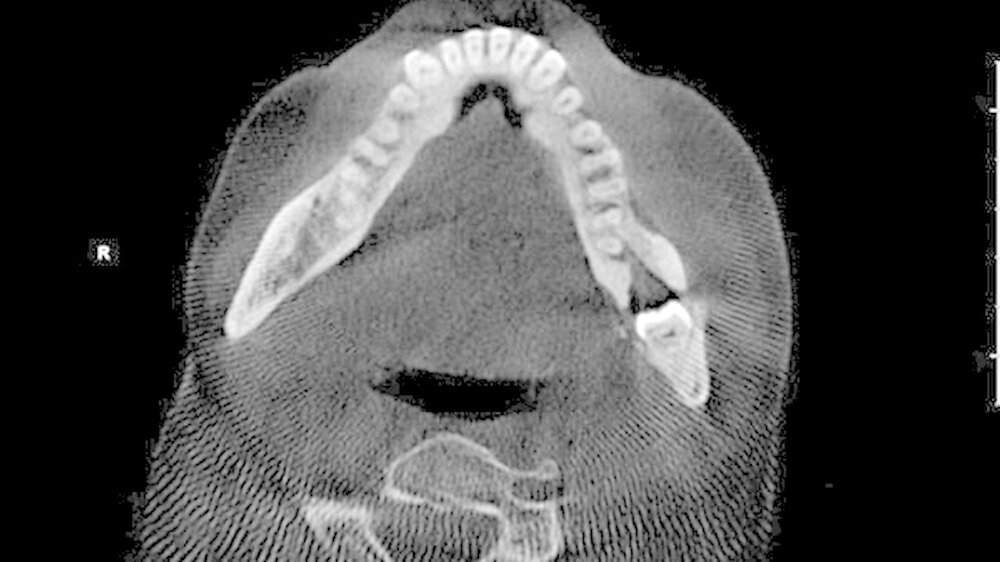

Es erfolgte durch den Hauszahnarzt zunächst eine intraorale Inzision von vestibulär sowie der Beginn einer oralen Antibiotikatherapie mittels Clindamycin 300 mg 1-1-1. Unter regredienter Symptomatik wurde die Patientin zur weiteren Therapie überwiesen. Nach ausführlicher Anamnese und klinischer Untersuchung wurde die Röntgendiagnostik durch eine Digitale Volumentomografie (DVT) zwecks exakter Lagebestimmung des retinierten Zahns 38 erweitert. Das DVT war insbesondere im Hinblick auf die anatomische Lagebeziehung zum Nervus alveolaris inferior aber auch zur Evaluation der Osteodestruktion nach stattgehabtem Entzündungsgeschehen indiziert.

Hierbei kam der Zahn 38 in seiner Längsachse rund 6 mm parallel zum Unterrand der Mandibula im Bereich des linken Kieferwinkels zur Darstellung. Weiterhin fiel eine perikoronare Transluzenz und die enge räumliche Lagebeziehung zum N. alveolaris inferior auf. Im weiteren Verlauf wurde die Indikation zur operativen Entfernung des Zahns von extraoral gestellt. Die Indikation zu diesem Eingriff war in der Sanierung des Infektionsherdes und damit der Prävention einer erneuten Entzündung und weiterer osteolytischen Schädigung des Unterkiefers begründet.

Der Zugangsweg von extraoral birgt zwar höhere Risiken für den Patienten, insbesondere die potenzielle Schädigung des N. facialis mit konsekutiver Einschränkungen der fazialen Motorik, war aber in dieser Situation aufgrund der sehr kaudalen Verlagerung des Zahns schonender, so dass mehr Knochensubstanz der Mandibula erhalten werden konnte.